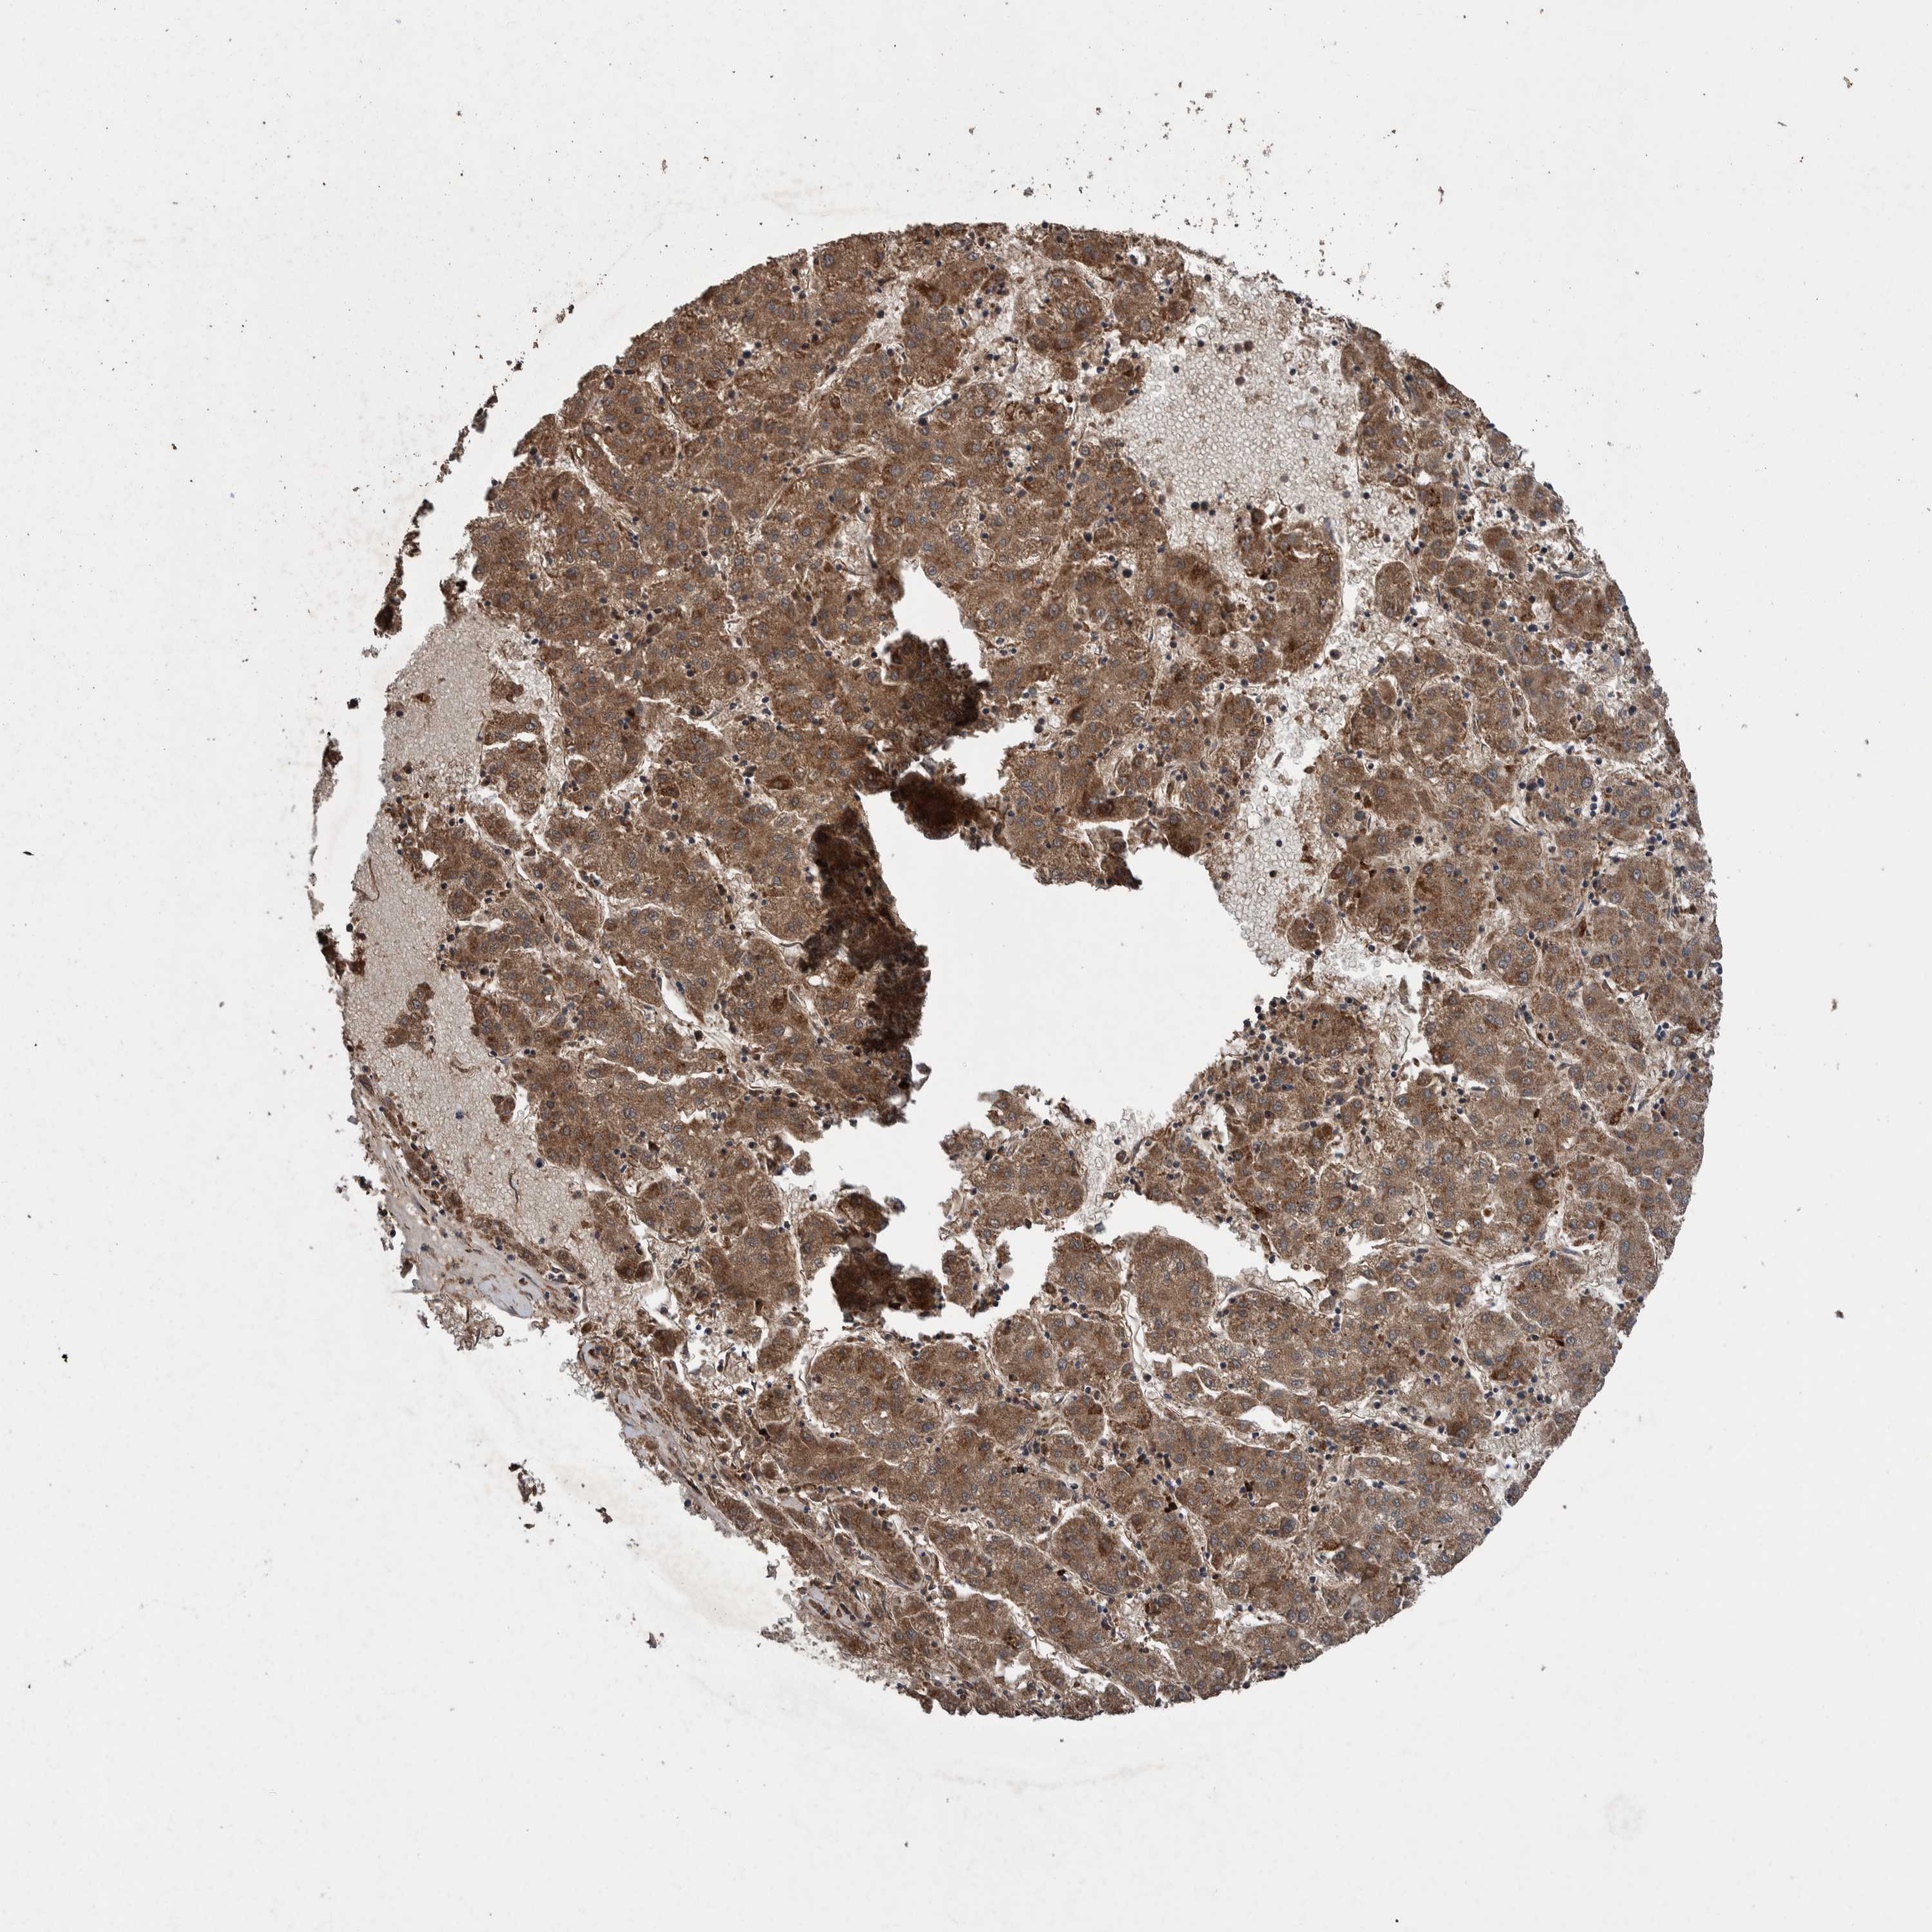

LIVER CANCER - Protein expressioni

A mouse-over function shows sample information and annotation data. Click on an image to view it in a full screen mode. Samples can be filtered based on level of antibody staining by selecting one or several of the following categories: high, medium, low and not detected. The assay and annotation is described here.

Note that samples used for immunohistochemistry by the Human Protein Atlas do not correspond to samples in the TCGA dataset.

Antibody stainingi

Antibody staining in the annotated cell types in the current human tissue is reported as not detected, low, medium, or high, based on conventional immunohistochemistry profiling in selected tissues. This score is based on the combination of the staining intensity and fraction of stained cells.

Each image is clickable and will lead to virtual microscopy that enables deeper exploration of all samples and also displays staining intensity scores, fraction scores and subcellular localization as well as patient and tissue information for each sample.

Antibody HPA023623

Antibody HPA066431

Staining

High

Medium

Low

Not detected

Intensity

Strong

Moderate

Weak

Negative

Quantity

>75%

75%-25%

<25%

None

Location

Nuclear

Cytoplasmic/membranous

Cytoplasmic/membranous,nuclear

Cholangiocarcinoma

Carcinoma, Hepatocellular, NOS